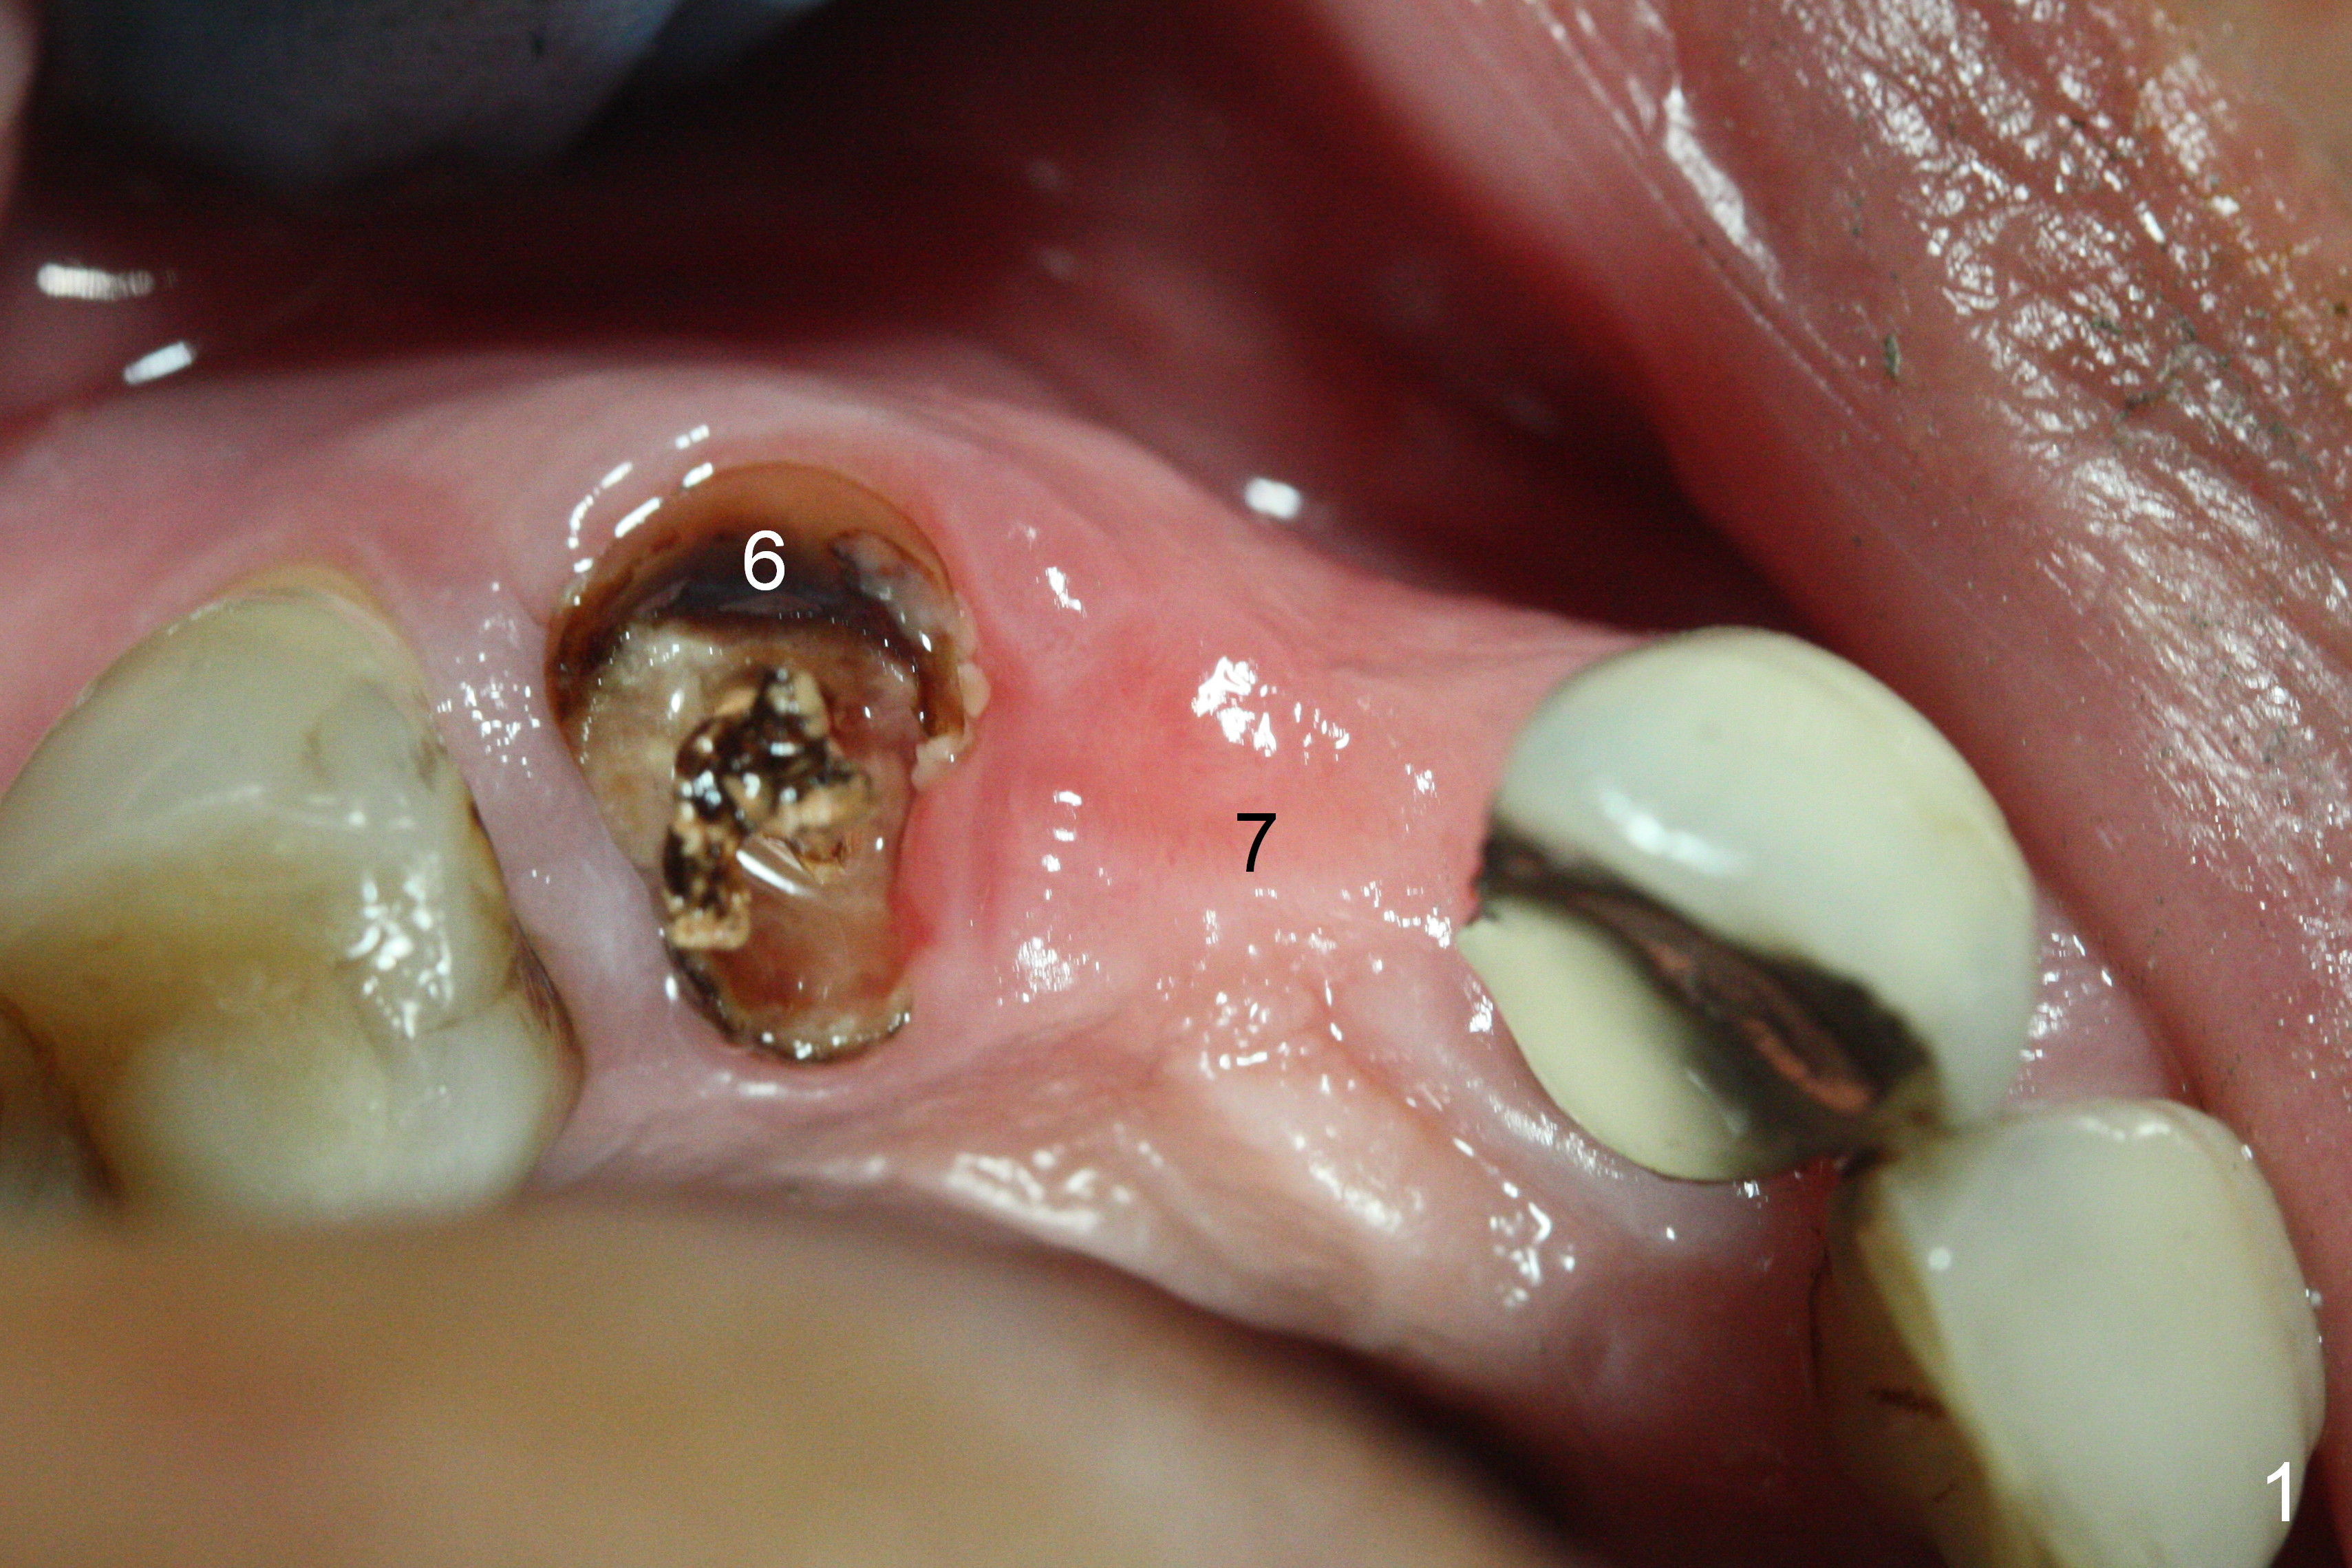

When the bridge is sectioned between #7 and 8, the tooth #6 is found non-salvageable (Fig.1).  Incision shows the atrophic buccal plate at #7 (Fig.2 arrowheads); to prevent the same feature from happening at #6 with thin buccal plate, the most buccal portion of the root is preserved (socket shield (Fig.2-4: *)).  The initial osteotomy is established in the palatal slope at #6 (Fig.5 circle) with 1.5 mm drill (Fig.6,7).  A portion of the root is visible in Fig.6 (arrowheads).  After sequential osteotomy with 2 mm, 3 mm (Fig.8) and 3.2 mm drills, a 4x15 mm implant is placed (Fig.10).  To accommodate the cross bite, the coronal portion of the implant (Fig.9 white circle) is positioned close to the socket shield.  It appears that the shield prevents the implant from encroaching the buccal plate.

Since the ridge at #7 is ~ 4 mm, a 2.5x14 mm 1-piece implant is placed (Fig.8) after 1.2 mm (Fig.7), and 1.5 mm drills at 12 mm and 2 mm drill at 8 mm.  Later the implant is placed deeper (Fig.10).  There is no bone loss 7 or 12 months postop, respectively (Fig.11,12).  After Diode gingivectomy, there is papillary formation (Fig.13).  No provisional is provided after impression (with the abutment torqued at #6) for oral hygiene.  With access holes at #6 and 7, crowns are bonded with minimal residual cement (Fig.14 <, which is removed later).  There is no hard (Fig.15,16) or soft (Fig.17 *) atrophy 26 months postop, i.e., 13 months post cementation, due to the presence of socket shield (Fig.15 <, as compared to Fig.1).  In fact the tooth #8 has mobility and fremitus (short root/poor crown/root ratio, Fig.16); occlusal adjustment is done 13 months post cementation.  The crown is dislodged 2 years 1 month post cementation; a prefabricated post is being tried in (Fig.18).  There is no atrophy, bone loss or infection at #6 (with socket sheath (*)) or 7 two years 5 months post cementation (Fig.20-27).